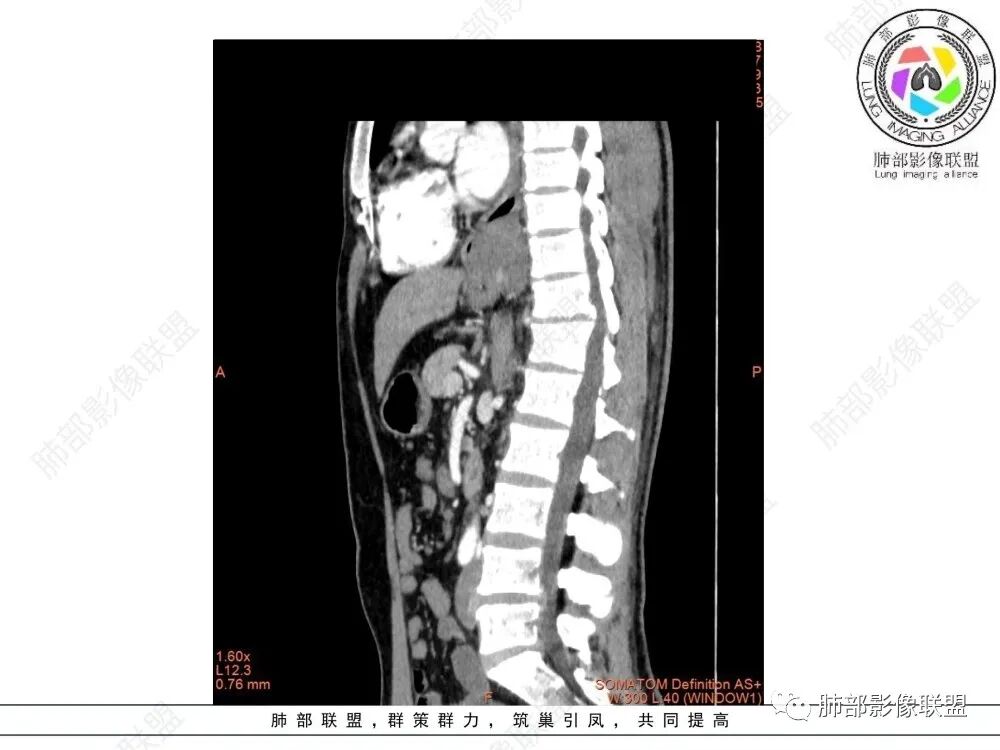

食管下段近贲门处肿块,食道受压变窄,粘膜无破坏,轻度强化,T2等低信号,考虑平滑肌瘤?神经鞘瘤?鉴别间质瘤。

定位后纵膈,实性密度,增强轻度强化,T1等低信号T2低信号,弥散未受限。钡餐造影,食道及贲门管壁柔和,造影剂通过顺畅。考虑神经鞘瘤。鉴别食道平滑肌瘤。

后纵隔占位,质地均匀,信号中等,与食管关系密切,弧形受压,食管粘膜完整。考虑平滑肌瘤或孤立性纤维瘤。鉴别:神经源性肿瘤。

食管平滑肌瘤是最常见的食管良性肿瘤,多见于男性,男女之比为2.6:1,高发年龄 30~60岁之间与食管癌相比,食管平滑肌瘤 的一个主要特点是病史相对较长,病情进展缓慢。病史最长者达10年余,平均 15.7个月,尽管病史较长,但大多数患者仍能进普食。食管平滑肌瘤的诊断一般比较容易,结合患者临床症状、食管造影及食管镜所见,一般均能得出正确诊断。食管造影主要为充盈缺损,病变与食管壁成锐角,粘膜线连续无破坏,管腔收缩扩张比较自如。钡餐造影敏感性高,但对食管壁间及食管周围情况难以判断。CT具有极高的密度分辨率,并且可以获得高质量的多平面重组图像,有利于食管壁间及食管周围情况的判断,表现为食管下段环绕管壁生长,偏心性或薄厚不均软组织密度肿块,密度均匀,内缘分叶状,管腔与正常食管壁构成不规则多角形扩张,增强动脉期无强化,多角度重建其病灶长轴与食管长轴不一致。由于食管壁在收缩状态下厚度约为5.6mm,扩张状态厚度不超过3mm,CT扫描时保持食管处于扩张状态可提高小病灶检出率。MR表现为T1加权等信号,T2加权稍高信号,可见高信号粘膜层,增强扫描轻度渐进性强化,密度均匀,无出血坏死。对于粘膜及周围脂肪间隙的判断具有明显优势。